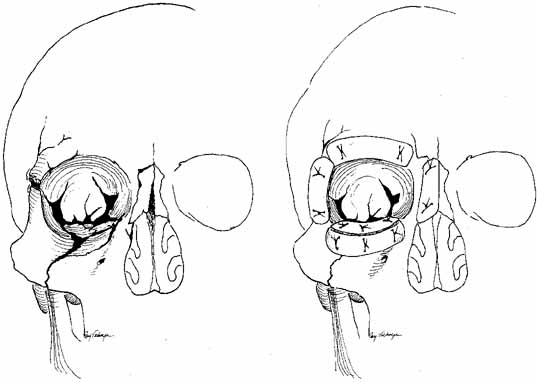

facilitates visualization and removal of the probe.  Fig. 22 Coronal sections through the nasal fossa and sinuses showing their sizes

and relationships through various ages. A. Age 5 weeks. B. Age 3½ years. C. Age 7 years. D. Age 9 years. (Bernstein L: Pediatric sinus problems. Otolaryngol

Clin North Am 4:128, 1971) Fig. 22 Coronal sections through the nasal fossa and sinuses showing their sizes

and relationships through various ages. A. Age 5 weeks. B. Age 3½ years. C. Age 7 years. D. Age 9 years. (Bernstein L: Pediatric sinus problems. Otolaryngol

Clin North Am 4:128, 1971)

for a general anesthetic. TECHNIQUES OF INSERTION. Passage and retrieval of the probes may be difficult. It is important to

recognize that intubation of the nasolacrimal system requires the physician

to negotiate several right-angle turns, particularly when

entering through the lower canaliculus. Furthermore, as the probe emerges

near the floor of the nose, it can be difficult to withdraw, especially

in the young child. This problem occurs because the inferior

meatus in a child is flat, and there is little space between the floor

of the nose, the lateral nasal wall, and the inferior turbinate (Fig. 22).73 Silastic intubation of the nasolacrimal duct can be particularly traumatic

if the probes are not malleable (Fig. 23). By the age of 3 years, more space has developed, but it is still

less than half of that present in the adult. For this reason, it can

be difficult to reach in and withdraw the probe with Silastic tubing

from the inferior of the nose without causing trauma to the nasolacrimal

duct in the interior of the nose. Enlarging this space by using a nasal

vasoconstrictor (4% cocaine or oxymetazoline) and

infracturing the turbinate toward the nasal septum, as previously described